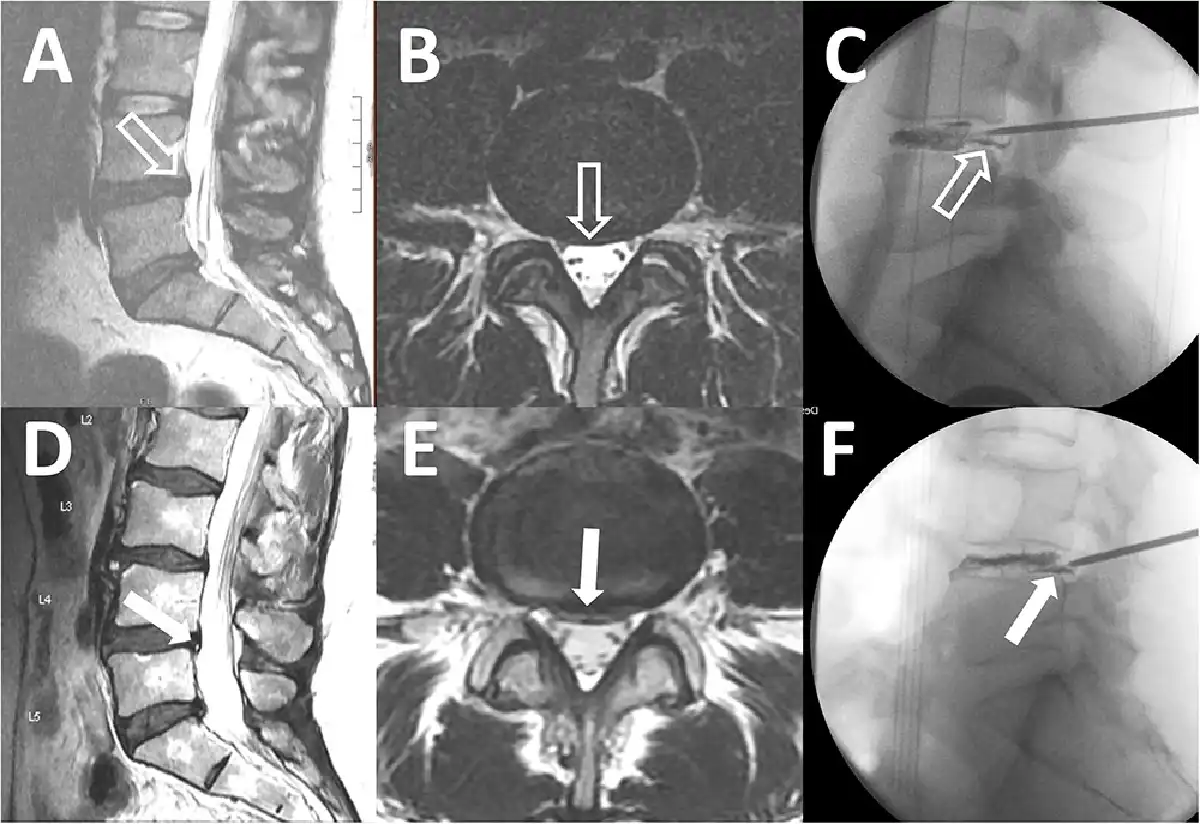

Subtle and obvious annular tears. T2 sagittal magnetic resonance imaging (MRI), T2 axial MRI, and the corresponding intraoperative discogram images show annular tears in patients with a subtle annular tear (A-C) and an obvious annular tear (D-F). A small bulging disc at L4-L5 without an associated high-intensity zone (HIZ) is indicated in panels A and B (open white arrows). Intraoperative discogram images reveal leakage of contrast through the annular tear (C, open white arrow). A bulging disc with an obvious HIZ is highlighted in panels D and E (solid white arrows). Intraoperative discogram images demonstrate leakage of contrast through the annular tear corresponding to the HIZ on MRI (F, solid white arrow). Note that there are also obvious annular tears at L5-S1 in panels A and D.

A third aspect of step B was for the spine surgeon to assess the lumbosacral MRI for the presence of a surgically treatable lumbosacral annular tear., All lumbosacral MRI had to have been of appropriate technical quality and performed within 12 months of clinical evaluation. The use of contrast material during the MRI procedure was not required unless there was previous lumbosacral spine surgery at the site of the annular tear. The following lumbosacral MRI categorization system was utilized. The patient was not considered a surgical candidate if there were no lumbosacral annular tears (Figure 3A) or if the patient had multilevel abnormalities where risks of surgery outweighed benefits (Figure 3B). The patient was a surgical candidate if the lumbosacral MRI revealed annular tears at 1, 2, or 3 spinal levels that could be treated by LESS. We then further classified the annular tear by severity per the following criteria: subtle if a disc bulge or protrusion was visualized but there was no accompanying high-intensity zone (Figure 4, A and B) and obvious if a high-intensity zone was visualized on the axial and sagittal T2-weighted images (Figure 4, D and E).

Patients with PGAD/GPD who met criteria for steps A to C in the management algorithm were considered candidates for endoscopic discectomy/annuloplasty with LESS. This technique is well described for the treatment of patients with back pain and radiculopathy.,, With a mixture of methylene blue and intravenous contrast media, a chromatodiscogram was performed to outline the annular defect (Figure 4, E and F). The annular defect on chromatodiscogram was identified in patients with subtle and obvious annular tears. The blue stain produced by the leakage of the methylene blue through the annular defect marked the pathologic area of the disc. Fragments of nucleus material trapped within the fissures of the posterior annulus were removed. Discrete tears and fissures in the annulus were ablated with the endoscopic radiofrequency probe (Trigger-Flex; Elliquence) and YAG-holmium probes (Lumenis). All patients were discharged the same day.

According to our criteria for severity, 10 patients were considered to have a subtle annular tear and 10 an obvious annular tear on lumbosacral MRI (Figure 4). As seen in Table 8, the most common locations were L4-L5 and L5-S1; 6 patients had annular tears at both these levels. These are common locations of lumbosacral spine injury, perhaps related to the transition zone between the flexible spine and the rigid sacrum., TFESI was performed in these patients, as determined by the multidisciplinary step-care management algorithm (Figure 1). All patients had a positive TFESI result, with a PGI-I score of 1, 2, or 3.